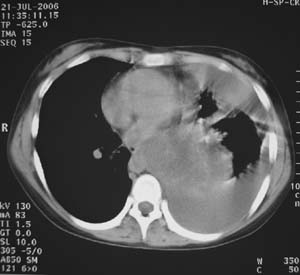

女性,17岁,一年前因股骨病变截肢,现胸憋。

左肺巨大肿块,内散在斑点状高密度骨化影,右肺见多发结节灶,双侧胸膜局限性增厚。有骨肉瘤病史,支持骨肉瘤手术后转移。